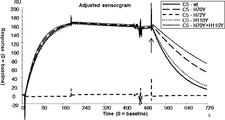

- Figure 2A illustrates BIACORE (registered trademark) sensorgrams of anti-C5 antibodies at pH7.4 (solid line) and pH5.8 (dashed line) to assess pH-dependency, as described in Example 3.2.

- CFA0305, CFA0307, CFA0366, CFA0501, CFA0538, and CFA0599 are antibodies grouped into epitope C, as described in Example 2.2.

- Figure 2B illustrates BIACORE (registered trademark) sensorgrams of anti-C5 antibodies at pH7.4 (solid line) and pH5.8 (dashed line) to assess pH-dependency, as described in Example 3.2.

- CFA0666, CFA0672, and CFA0675 are antibodies grouped into epitope C

- CFA0330 and CFA0341 are antibodies grouped into epitope B, as described in Example 2.2.

- 305LO5 is a humanized antibody of CFA0305, as described in Example 2.3.